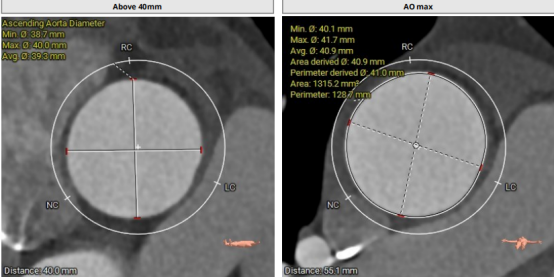

CT結(jié)構(gòu)評估

采取局麻+鎮(zhèn)靜麻醉方式,避免氣管插管對循環(huán)打擊;預(yù)裝VenusA L26瓣膜,患者心功能較差不進行球囊預(yù)擴張,直接放瓣膜;升主動脈稍寬,注意器械通過,必要時snare輔助;建議行左冠保護;右股動脈作為主入路。

根部造影:瓣葉活動度較差,左冠口較低,雙側(cè)冠脈灌注正常,升主動脈稍擴張。